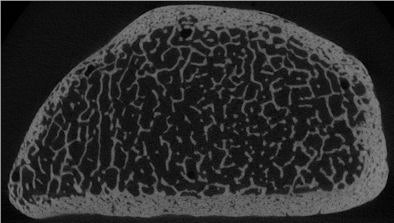

| Trabecular structure of the human radius bone at micro-CT, 18-µm spatial resolution. Image courtesy of Dr. Ahi Sema Issever and Dr. Patrick Rogalla. |